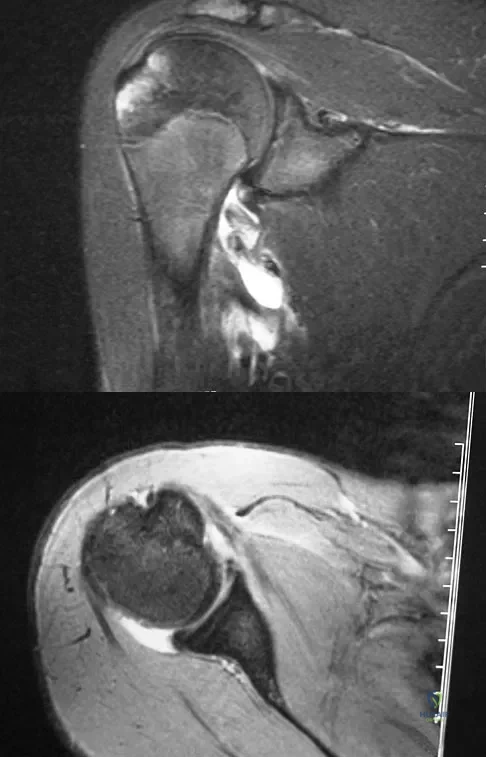

Figures 11a and 11b show the AP and lateral radiographs of a 32-year-old patient on hemodialysis who has increasing elbow pain and a visibly growing mass over the extensor surface. Figure 11c shows the photomicrograph of the biopsy specimen. What is the most likely diagnosis?

The radiographic findings are classic for tumoral calcinosis; they are not consistent with myositis ossificans, fungal granuloma, or hemochromatosis. The condition typically appears as large aggregations of dense calcified lobules confined to the surrounding soft tissues. Hyperphosphatemia is a fundamental factor in many patients with this condition. Tumoral calcinosis also occurs in the setting of chronic renal failure when mineral homeostasis is not controlled. The histologic appearance is essentially a foreign body granuloma reaction. Multilocular cysts with purplish amorphous material are surrounded by thick connective tissue capsules. The fibrous walls contain numerous foreign body giant cells. Surgical excision is indicated if the tumor causes discomfort or interferes with function. Sisson HA, Murray RO, Kemp HBS (eds): Orthopaedic Diagnosis: Clinical, Radiological and Pathological Coordinates. New York, NY, Springer-Verlag, 1984.